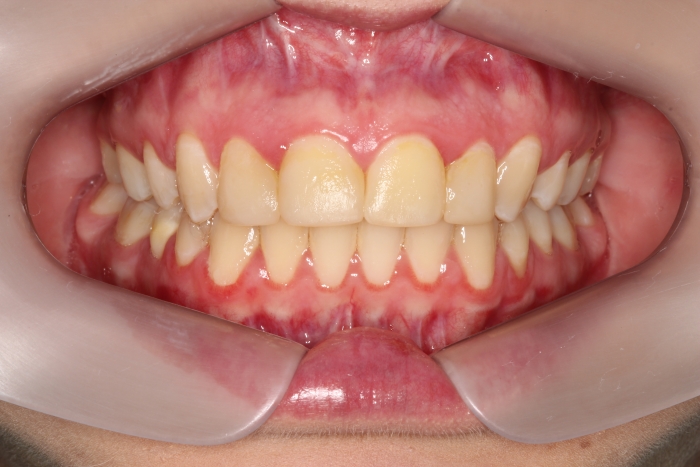

Mordida inicial